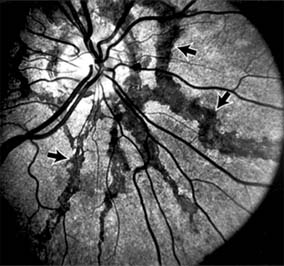

Figure 10-5

Figure 10-5: Presumed ocular histoplasmosis syndrome with active disease (large arrows) and an inactive pigmented macular scar (small arrow). Peripapillary pigmentation (curved arrow) is also present.